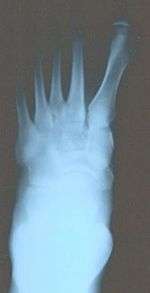

It is leaning of the first metatarsal bone away from the second metatarsal and towards the opposite foot (Fig. 1). As it leans over, its head sticks out to form the bunion bump and it also widens the forefoot to cause shoes feeling too tight. Thus when bunion pain becomes unmanageable, surgical correction is to narrow the forefoot by repositioning of the first metatarsal head back to its normal position. This can be done by osteotomy (bone-breaking), soft tissue (non-osteotomy) or fusion techniques.

Syndesmosis procedure addresses specifically the two fundamental problems of metatarsus primus varus deformity that gives rise to the bunion deformity. They are leaning and instability of the first metatarsal bone . Syndesmosis procedure uprights the leaning first metatarsal bone with strong binding sutures between it and the second metatarsal bone (Fig. 2) and then also stabilizes it uniquely by creating a fibrous connecting bridge between these two bones (Fig. 3,4). First metatarsal bone can be readily realigned is because by definition of the metatarsus primus varus deformity its first metatarsal is abnormally loose and mobile.